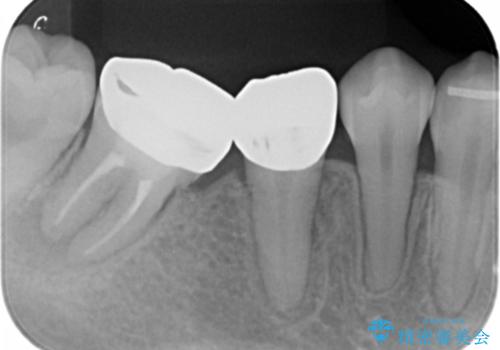

- 見栄えが悪く、歯ブラシのしづらい銀歯を白くしたい、とセラミック治療を希望され来院されました。

歯が傾いているため、歯間ブラシや歯ブラシのしやすさを考慮し、汚れの溜まりにくいようなクラウン設計を行います。